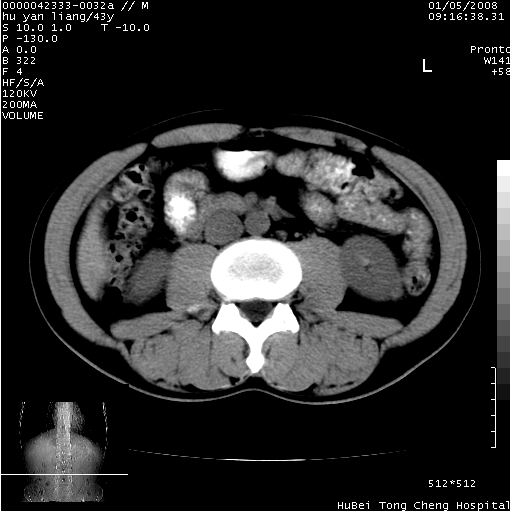

患者 男,43岁。右上腹不适1年余。既往有“肝右叶肝脓肿”病史,经保守治疗后痊愈。

b超提示:1)肝右叶肝内胆管结石。2)肝右叶占位性病变待排。

上中腹部ct轴位平扫+增强扫描(层厚10mm,螺距1.0,重建间隔10mm),图像如下:

肝右上叶偏后方较大团片状钙化灶,支持:肝脓肿后遗改变!

肝右叶钙化灶,考虑为肝脓肿后遗症。

肝右叶后段团块状钙化灶,结合病史考虑肝脓肿痊愈后表现。